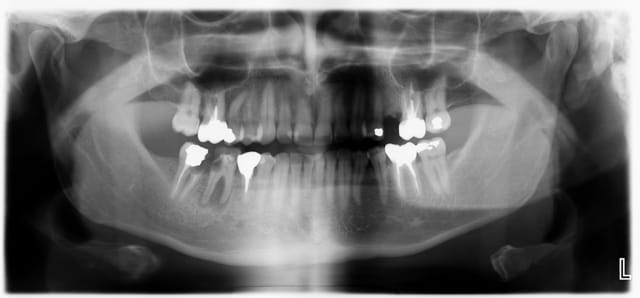

-suite à l'endo+rcr de la semaine dernière sur 46, ce matin: prep, pro 46 47 et amputation de la racine mésiale de 47 en 45min. Sur la radio, il reste encore un peu (;-)) de temp bond.

Retour dans 3 mois pour la suite des opérations.

Pano shpohv - Eugenol

46 47 yiqmod - Eugenol